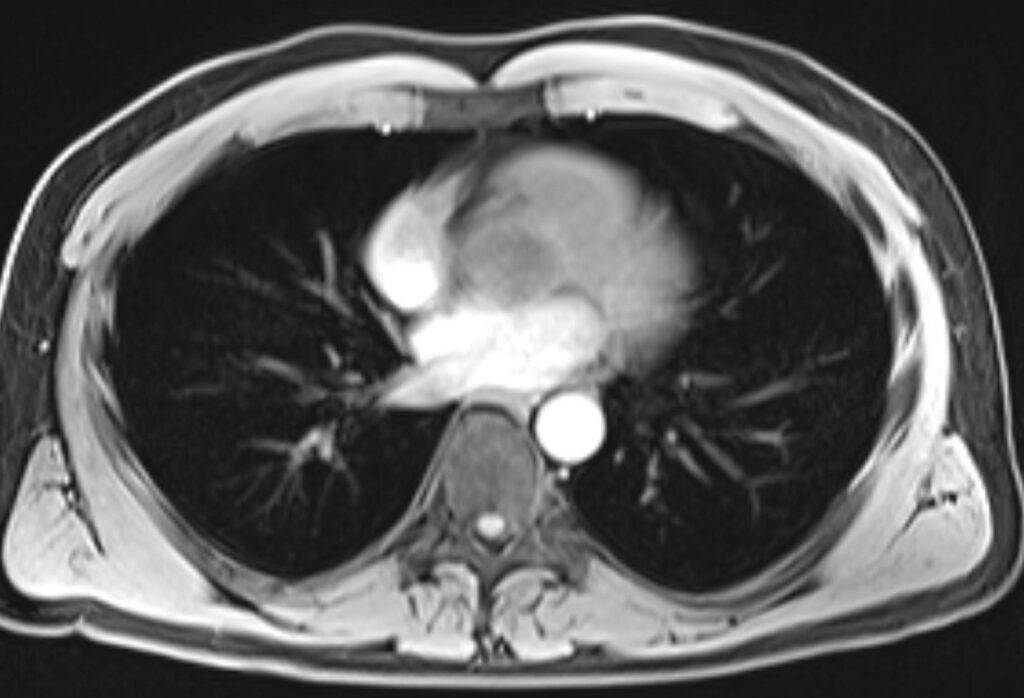

Eine Magnetresonanztomographie des Brustkorbs, kurz die MRT Thorax genannt, ist ein medizinisch bildgebendes Verfahren. Die MRT Thorax Untersuchung stellt mithilfe von Magnetfeldern und Radiowellen insbesondere die Lungenflügel, das Herz, die großen Blutgefäße und das Mediastinum detailliert dar. Vor allem bei Verdacht auf Tumore oder andere komplexe Erkrankungen im Brustbereich kann eine MRT Thorax aufschlussreich sein.

Bei der Thorax MRT-Untersuchung wird ein Hochfrequenzsystem verwendet, das die Ausrichtung dieser Atomkerne ändert. Während die Kerne in ihre ursprüngliche Position zurückkehren, senden sie Signale aus. Diese Signale werden von speziellen Detektoren aufgefangen und in Bilder umgewandelt. Das Ergebnis sind detaillierte Querschnittsbilder des Brustkorbs, die es ermöglichen, die inneren Strukturen wie Lungen, Herz, große Blutgefäße und das Mediastinum in hoher Auflösung darzustellen.

Die MRT Thorax erstellt viele Bilder von verschiedenen Schichten des Brustbereichs, die anschließend zu einem dreidimensionalen Bild zusammengesetzt werden.

Verdacht auf Mediastinaltumor: Das Mediastinum ist der Raum zwischen den Lungenflügeln, in dem sich das Herz, große Blutgefäße und andere wichtige Strukturen befinden. Tumoren in diesem Bereich können durch eine MRT präzise lokalisiert und charakterisiert werden.